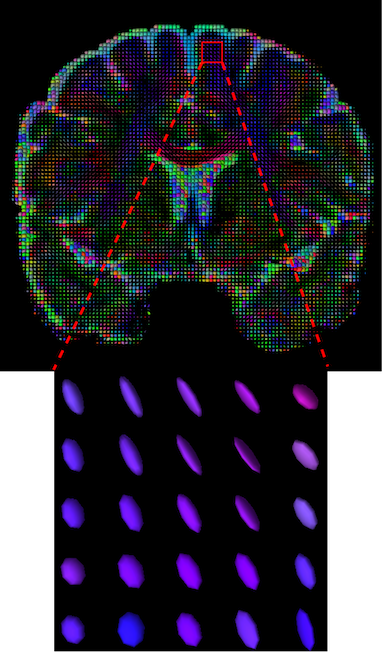

III-D Qualitative Results

The visualization of inpainted results (showing the whole diffusion tensor for each voxel) generated from different models are demonstrated in Figure 3, where the tensor is represented in RGB coding that colours red, green and blue represent diffusion in the x, y, and z axes respectively. One typical example of reconstruction in the disrupted ROIs has been zoomed for visualization. Compared to the ground truth, TW-BAG is able to generate more distinct orientations following the original distribution and intensity across sagittal, coronal and axial views, which could demonstrate water diffusivity (denoted by eigenvalues of tensor model) more accurately. As indicated in Figure 4, the boundaries and textures of the FA map for TW-BAG are less blurry than the other competing models, validating the effectiveness of TW-BAG from a neuroscience perspective.